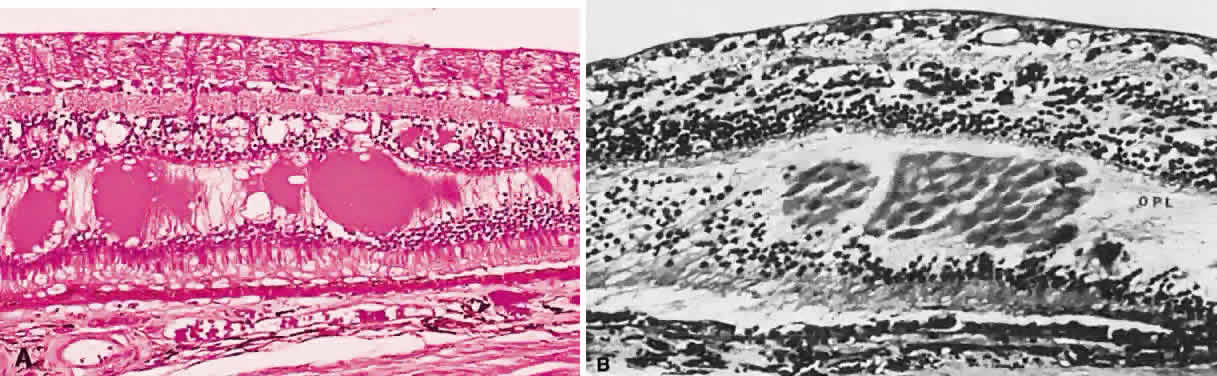

Necrotic retina has a white appearance. Necrosis may result from a variety of inflammatory conditions, including viral, fungal, and protozoal (Toxoplasma) retinitis. Each type of retinitis appears, in part, as a white retinal lesion. Cytomegalovirus retinitis (Fig. 24) resembles a pizza pie with an admixture of white (retinal inflammation) and red (hemorrhage) colors (Fig. 25). The retinal abscesses of fungal retinitis are white. Likewise, the satellite lesion of retinochoroiditis caused by active Toxoplasma (the choroidal inflammation is merely in response to the primary retinal infection) is white (Fig. 26). The white appearance of a lesion from inactive Toxoplasma results from the destruction of neurosensory retina, retinal pigment epithelium, and choroid to permit a direct view of the sclera (Fig. 27). Necrosis in retinal-derived neoplasms is white; the appearance of regressed (necrotic) retinoblastoma often is described as “cottage cheese.”10

Fig. 24. A. Histologic section of cytomegalic inclusion retinitis. The characteristic inclusions cannot be seen at this magnification. Compare the appearance of viable healthy retina (left of arrow) with necrotic retina (right of arrow). The admixture of necrotic retina (clinically white) with hemorrhage (clinically red) accounts for the ophthalmoscopic appearance of this entity. B. Cytomegalovirus retinitis. Histologic section of sensory retina demonstrating massive necrosis involving all layers. (Courtesy of Ralph C. Eagle Jr, MD, Philadelphia, PA)

Fig. 25. Fundus photograph of cytomegalovirus retinitis with the classic admixture of retinal infection (white) and hemorrhage, giving the so-called “pizza-pie” appearance.

Fig. 26. Fundus photograph of toxoplasmosis chorioretinitis scar with white (active) satellite lesion.

Fig. 27. Fundus photographs of quiescent toxoplasmosis chorioretinitis scar. The white center is the result of destruction of the neurosensory retina, retinal pigment epithelium, and choroid, leaving only the sclera in view.